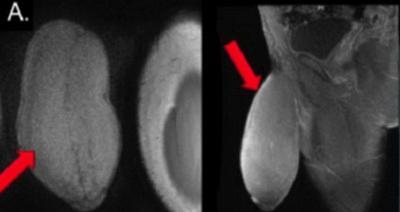

Дэлхийд анх удаа эрэгтэй хүн бэлэг эрхтнээ жижигрүүлэх мэс засал хийлгэсэн тухай “Dailymail” мэдээллээ. Америкийн иргэн 17 настай залуу хүүд бэлгийн ажил үйлдэх нь бүү хэл, спортоор хичээллэхэд нь асар том эрхтэн нь садаа болдог байжээ. Тиймээс эмнэлэгт хандаж бэлэг эрхтнээ жижигрүүлэхийг хүссэн аж. Эмч нар ч анх удаа ийм тохиолдолтой таарсан бөгөөд уг мэдээлэл олон нийтийн сүлжээнд ихээхэн шуугиан тариад байна. Хүүгийн эрхтэний урт 18 см, тойргоороо бараг 25 см хүрч байсан нь үнэхээр эмч нарыг гайхшруулсан байна.

Ийм эрхтэн босохоороо үнэхээр хүндрэлтэй гэж эмч нарт ярьжээ. Мэс засал амжилттай болсон бөгөөд хүү ч сэтгэл хангалуун байгаа аж.